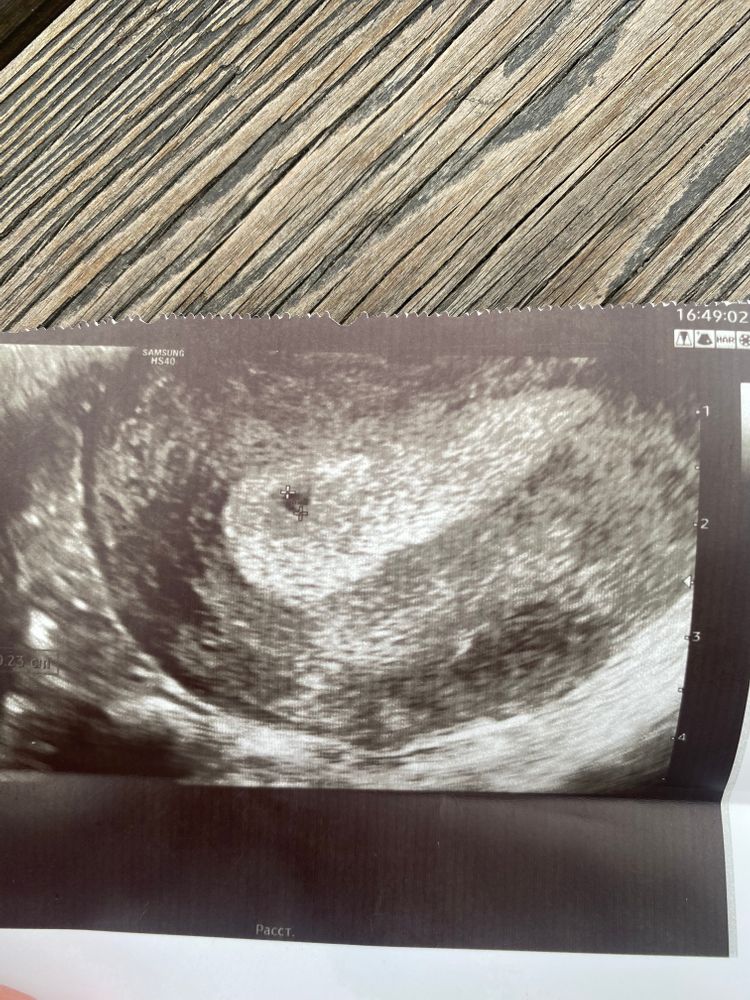

Это узи моей второй беременности)

и тут так же не знали есть ли беременность 🤷🏼♀️

уже 2 года бегает 😜

про тесты поспорила бы ) у меня 2-е детей

и со второй дочкой тесты и хгч долго не показывали )и вот вам пример

сегодня приехала моя врач посмотрела меня и сказала что исключить беременность она не может т.к за 2 дня точка стала больше была 1.8 мм стала 2.4 мм

так что через 5 дней будет все точно понятно